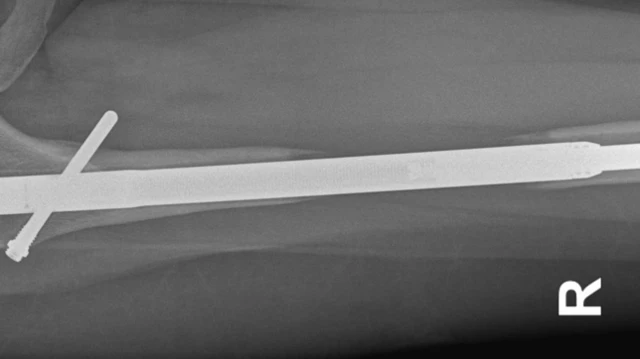

इस प्रक्रिया में थोड़ा दर्द होता ही है क्योंकि पैर की हड्डी को दो हिस्सों में तोड़कर उनके बीच मेटल की रॉड लगाई जाती है.

धीरे-धीरे दोनों हिस्सों के बीच लगे मेटल के इस रॉड की लंबाई बढ़ाई जाती है, जिससे मरीज़ की लंबाई बढ़े.

आम तौर पर हड्डियों के ये दोनों हिस्से फिर से जुड़ते हैं और इनके बीच खाली जगह को भरते हैं. यह सिर्फ शुरुआत होती है, लेकिन इसका ऑपरेशन बहुत जटिल होता है.

छह सप्ताह बाद हुए स्कैन में पता चला कि उनके दाहिने पैर में हड्डियों का बढ़ना रुक गया था. इस पैर में फीमर के दो टुकड़े रॉड से जुड़े हुए थे.

इलेन जब डॉक्टर से मिलीं तो उन्होंने एक और ऑपरेशन मिलान के क्लीनिक में तय किया. अप्रैल 2017 में उन्होंने इलेन के बाएं पैर को बड़ा करने की प्रक्रिया शुरू की. इस दौरान दाहिने पैर में बोन मैरो डाला गया ताकि हड्डी के विकास को प्रेरित किया जा सके.